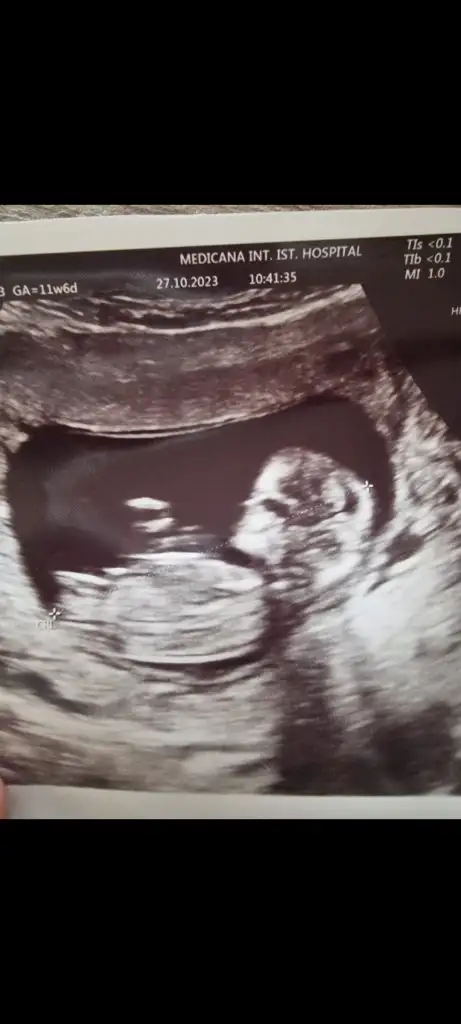

Merhaba 11 hafta 6 gün çatlamak üzereyim bana da bakabilir misiniz?Evet erkek bu bebiş

KızMerhaba 11 hafta 6 gün çatlamak üzereyim bana da bakabilir misiniz?